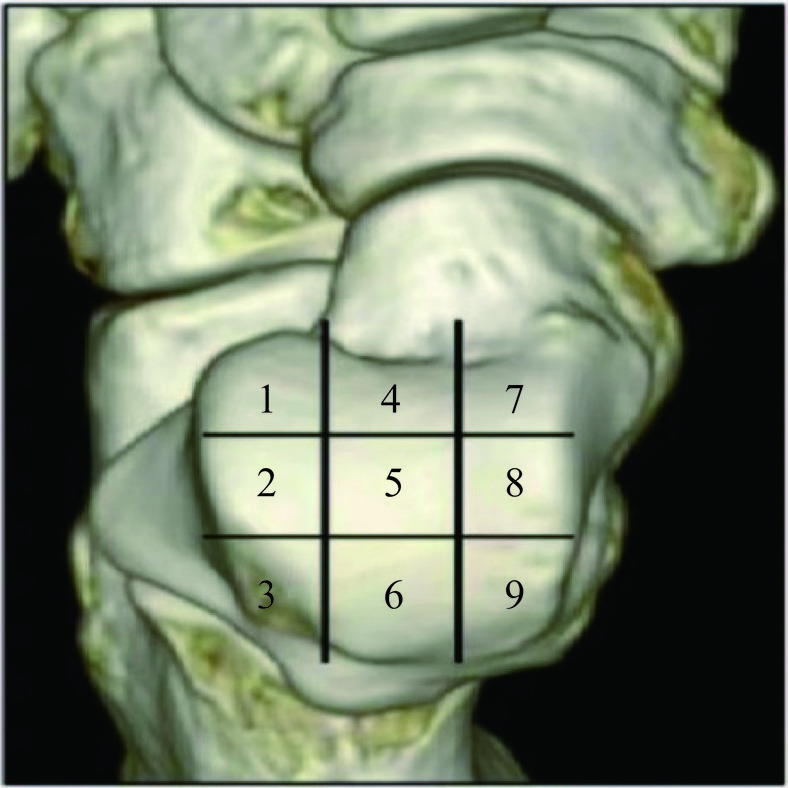

为方便记录病变的区域及范围,将距骨穹隆表面划为九宫格分区[6](图1)。DECT三维重建,利用轴位的分区进行矢状位及冠状位的定位。MRI同样根据轴位,使用定位线对矢状位及冠状位进行病灶定位。采用Hepple等改良的MRI分期标准。为方便研究、比较,我们将阴性的区域,定为0期。

本研究由4名骨科经验丰富的放射科主治医生A、B、C和D,分别对MRI及DECT图像进行分期。A医生对30例MRI图像进行诊断及分期。B医生和C医生,在不知MRI结果的情况下,对0.5系数DECT融合图和VNCA图像进行视觉评估分期。DECT图像评估时,首先观察0.5系数融合图及其三维重建图像,对OLT进行Ⅰ、Ⅱ、Ⅳ、Ⅳ、Ⅴ的大体分期,再观察VNCA图像,把Ⅱ期分为ⅡA期和ⅡB期,有骨髓异常信号为ⅡA期,无骨髓异常信号为ⅡB期。在VNCA图像上,观察关节软骨下的骨髓,正常骨髓颜色为蓝紫色,异常的骨髓区域,表现为边缘模糊的绿色(图2)。